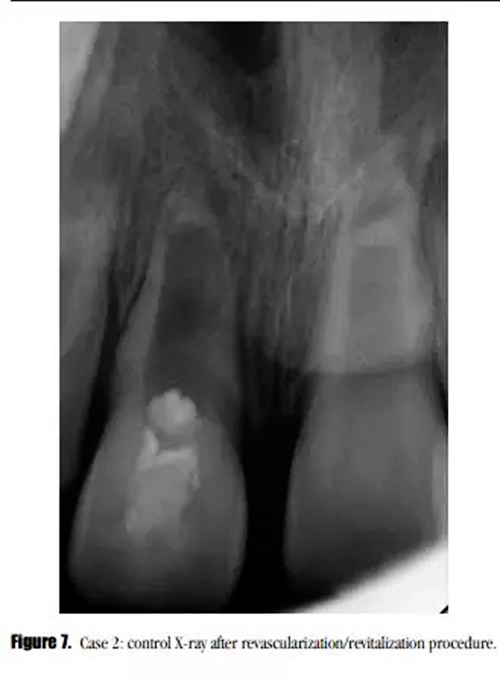

采用與之前所述一致的方法對(duì)患牙進(jìn)行治療,患者癥狀消失。在初次就診之后的3個(gè)月后,我們開始了第二次治療。術(shù)后X線顯示,牙根進(jìn)一步發(fā)育,沒有牙根根管壁的沉積,MTA塌陷進(jìn)入到血凝塊中。(圖7)